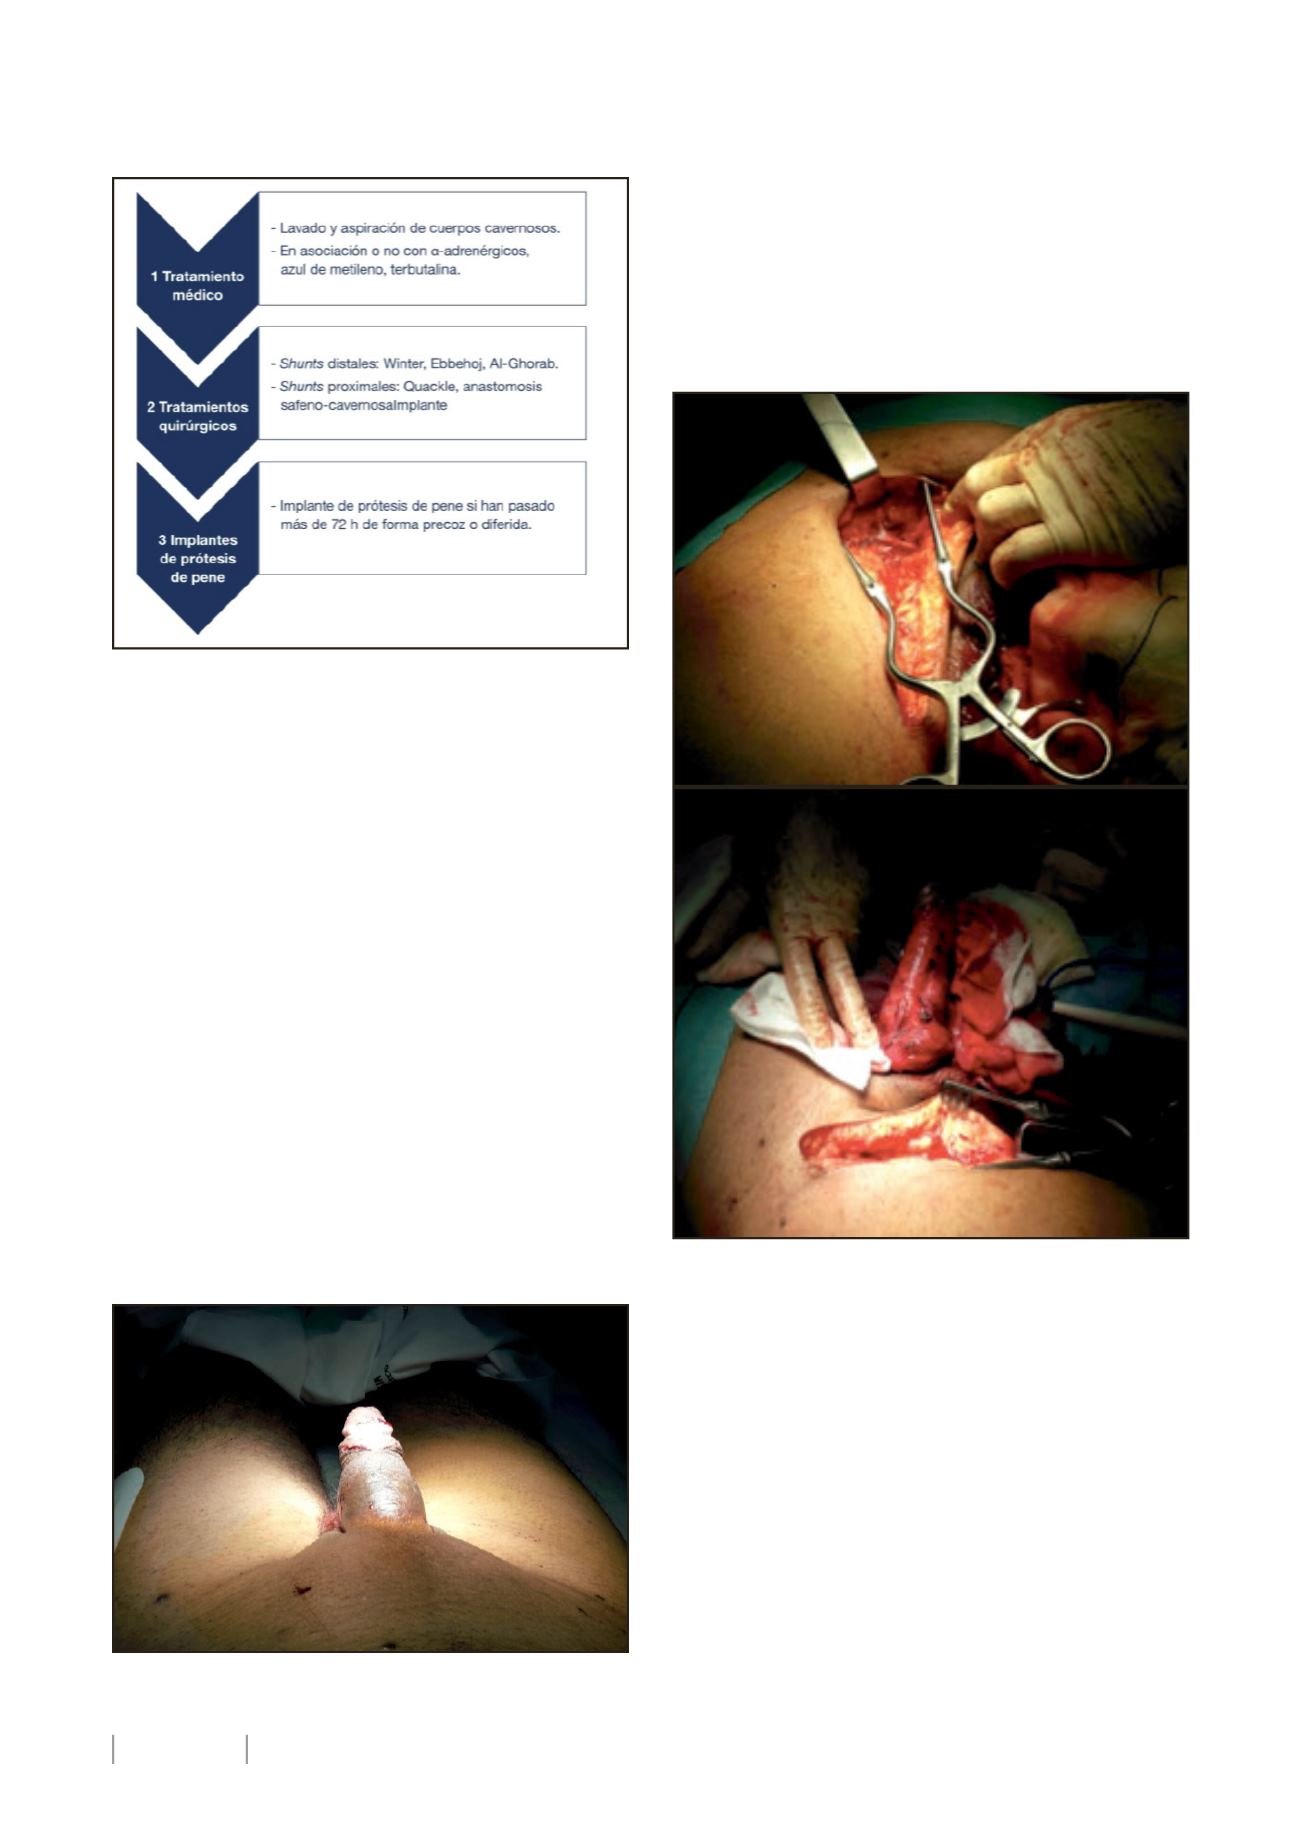

A la exploración, el paciente presenta erección completa

del pene, sugerente de priapismo (ver figura 2). En la analítica,

no se encontraron alteraciones relevantes. La gasometría de

cuerpos cavernosos indicaba pH acidótico. La Ecografía-Doppler

descartaba etiología arterial del priapismo. Ante tales hallazgos,

el paciente es diagnosticado de priapismo isquémico y se decide

tratamiento quirúrgico emergente.

Ante la ausencia de mejoría, se avisa al Cirujano Vascular

de guardia. Realizamos, bajo anestesia general, una derivación

safeno-cavernosa derecha según la técnica de Grayhack (2). Ver

figura 3:

•

Disección de 10-15 centímetros de vena safena

proximal. Ligamos extremo distal y lo seccionamos,

manteniendo su drenaje hacia la unión safeno-

femoral.

Tunelización subcutánea y abordaje de la albugínea

mediante incisión en la base del pene.

Anastomosis safeno-albugínea mediante sutura

continua con monofilamento 6/0.

El procedimiento tuvo éxito técnico, produciéndose la

detumescencia del pene en menos de 72 horas. No hubo com-

plicaciones a nivel local ni sistémico ni complicaciones trom-

boembólicas. Fue dado de alta a los 4 días sin recidiva y con la

derivación funcionante.

Figura 1. Manejo del priapismo Venooclusivo.

Figura 2. Pene en erección al ingreso.

Figura 3. Shunt safeno-cavernoso.